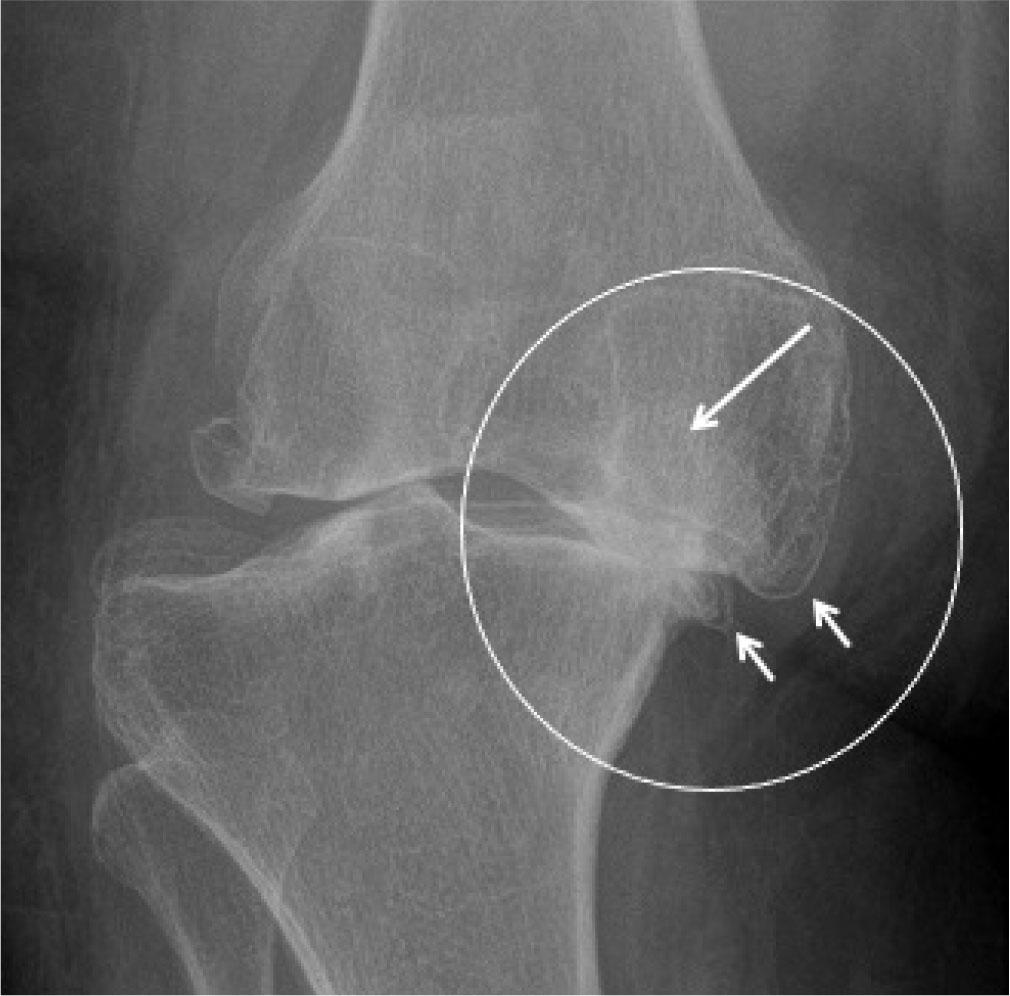

Osteoarthritis is the most widespread form of arthritis. The most commonly affected joints are the weight-bearing type, or the ones used repetitively – the hip, knee, foot, and hand. Radiography is the primary imaging modality to evaluate OA. Radiographic features include marginal osteophytes, asymmetrical joint space narrowing, subchondral sclerosis, and subchondral cysts (Fig. 20). Joint space narrowing is an indirect surrogate marker to assess articular cartilage loss on radiographs. Increasingly, HRUS and MRI are being utilized for the evaluation of soft tissues in the OA joint.

Fig. 20.

Severe osteoarthritis (OA). AP radiograph of the right knee shows marginal osteophytes (small arrows), medial joint space narrowing (circle), subchondral sclerosis, and subchondral cysts (long arrow)